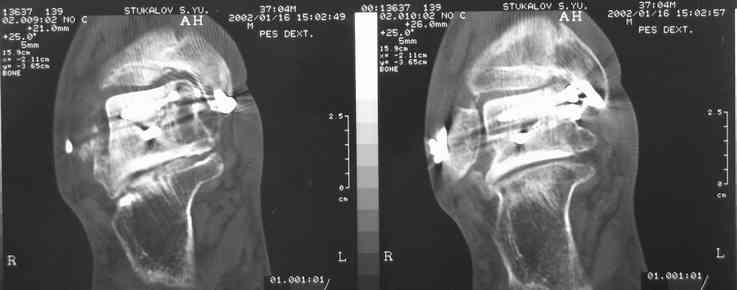

В Вашей ситуации мы произвели открытую репозицию и фиксацию металлоконструкциями. Все зажило первично, посттравматического дефартроза избежать не удалось. Пациент от артродезирующих операций в отдаленном периоде отказался.

Пациент отказался от артродезирующих операций потому что его устривает качество жизни или были какие-то другие причины (в итоге таран выглядит жутковато)